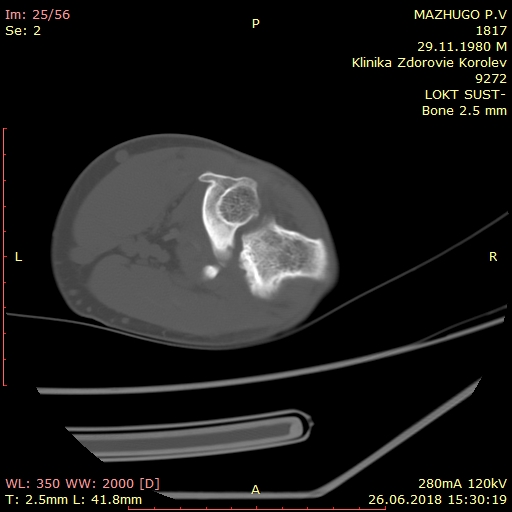

> Пациенту 38 лет. Травма в сентябре 2017 - вывих локтевого сустава с

> закрытым оскольчатым переломом головки луча. В одной из больниц Москвы

> произведено вправление вывиха, резекция головки луча. Иммобилизация гипсом

> локтевого сустава, по рекомендации клиники